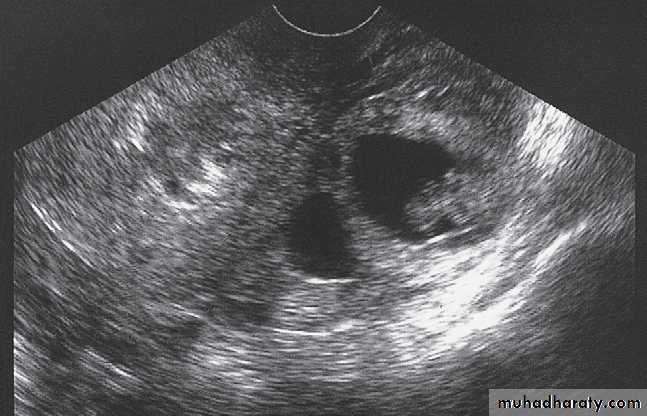

Endometriosis is usually seen as a cystic mass with homogeneous internal echogenicity in the adnexal region and/or pouch of Douglas corresponding to the chocolate cysts found on pathological examination .

On MRI There are characteristic appearances due to recurrent haemorrhage into endometriomas and there is often in-drawing of the rectum towards the pouch of Douglas due to the development of fibrous adhesions.